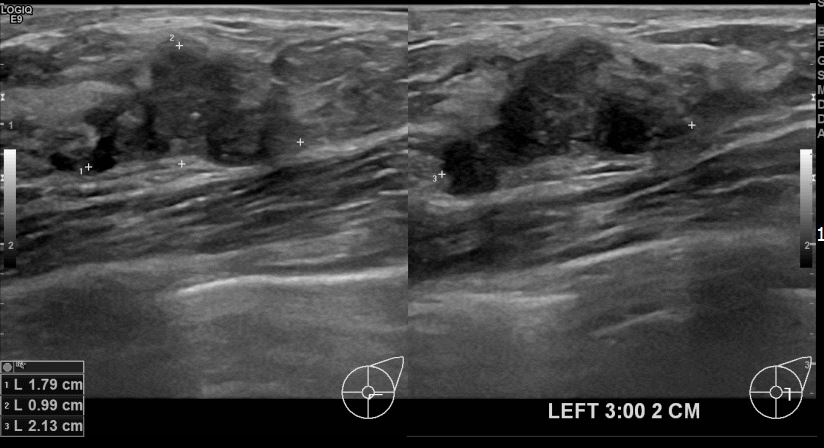

상기환자는 중국에서 유방암확진을 받은 후에 서울에서 치료를받고자 내원하신 40대 여성분입니다. 침윤성유방암진단되어 3차의료기관 의뢰드렸습니다.